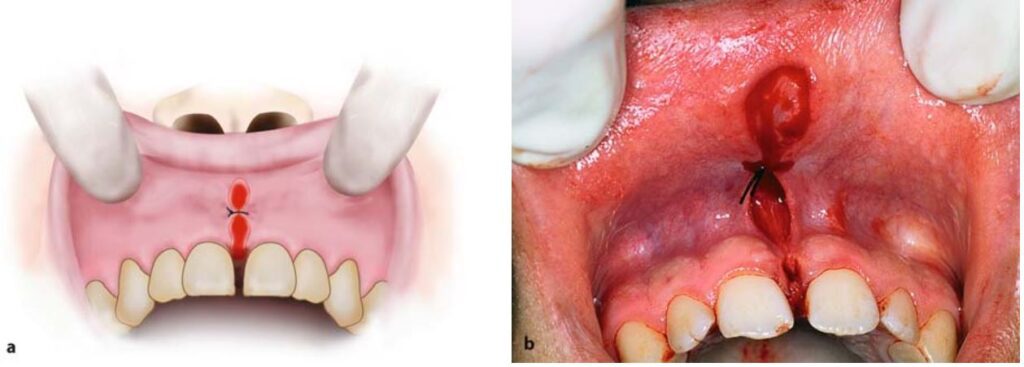

Thực hiện khâu vết thương sau khi đã dùng kéo để làm giảm căng mô quanh bờ tổn thương (H10.80 – 10.82).